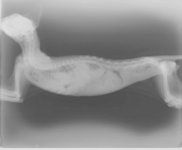

Endlos rollen heute die Tränen aus den Augen der Kinder, die vor wenigen Tagen den kleinen Kater Alex beim Spielen gefunden hatten. Sein Zustand war sehr schlecht, medizinische Versorgung dringendst notwendig und so haben wir ihn ohne zu zögern bei uns im NLR aufgenommen. Nach einer umgehenden Röntgenuntersuchung zeigte sich das ganze Ausmaß seiner schweren Verletzungen. Eine Zwerchfellhernie (Zwerchfellriss) machte eine zeitnahe Operation unumgänglich. Für die schwierige Operation benötigt man ein Narkosegerät mit aktiver Beatmung, das uns leider nicht zur Verfügung steht. Eine erfahrene griechische Kollegin in Chania führt solche Operationen durch. Uns war bewusst, dass sein Zustand kritisch war und es keine Überlebenschance ohne OP gab. Eine zeitnahe Operation war unumgänglich. Heute war es dann soweit. Der OP Termin im 80km entfernten Chania war bestätigt und ich machte mich mit dem kleinen Kater Alex auf den Weg. Eine schwieriger Eingriff stand ihm bevor, aber die einzige Möglichkeit um zu überleben. Ein mulmiges Gefühl, Ungewissheit und Sorge begleiteten mich auf der Rückfahrt. Meine Gedanken waren bei Kater Alex. Kurz nach meiner Rückkehr in Rethymno bestätigte sich dieses Gefühl. Der kleine Kater Alex hatte es nicht geschafft und ist während der Operation verstorben. Wir alle sind tief traurig.